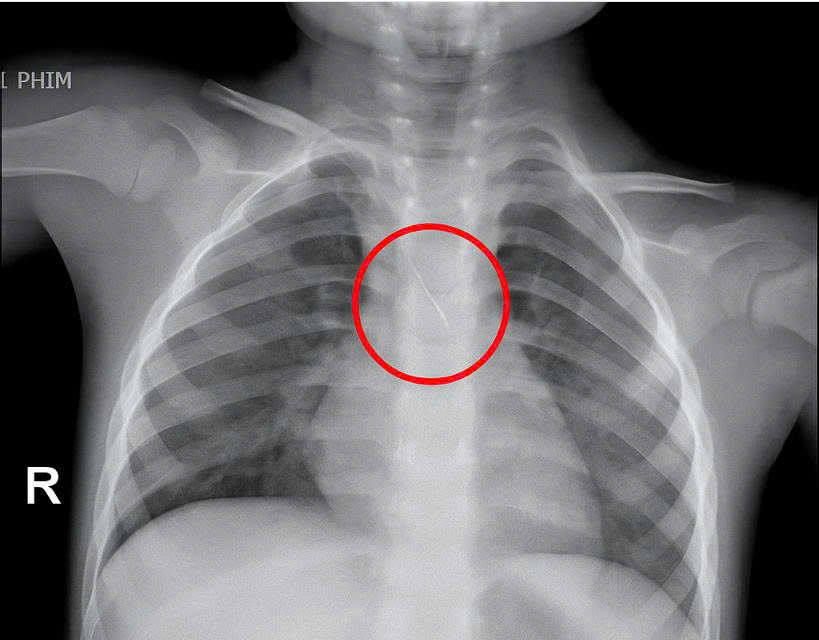

Dị vật trong đường thở cháu bé.

Trước đó, bé nhập viện trong tình trạng ho nhiều, ho sặc. Qua thăm khám và chụp phim, các bác sĩ xác định bé bị sặc kim chọc tủy dài khoảng 22mm, vị trí mắc tại góc carina, nơi chia đôi khí quản. Đây được đánh giá là ca cấp cứu nguy hiểm.

Bệnh viện kích hoạt hội chẩn liên khoa và quyết định tiến hành nội soi phế quản cấp cứu. Dị vật được phát hiện với một đầu nhọn cắm vào đoạn dưới khí quản, đầu còn lại nằm trong phế quản gốc trái.